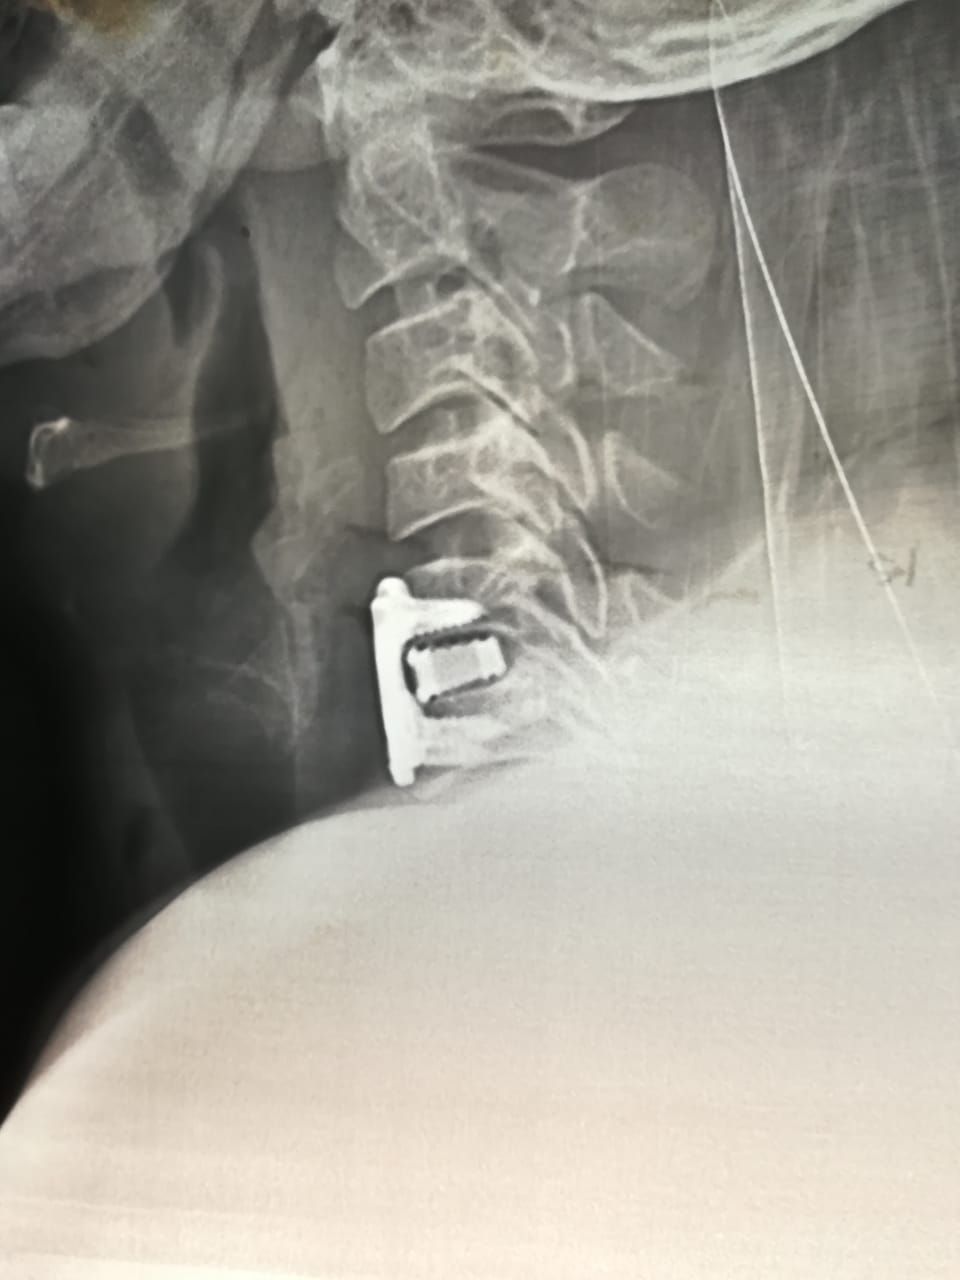

Cirugía de Columna Vertebral (Centro Médico Nacional de Occidente 2016)

• Cirugía de columna